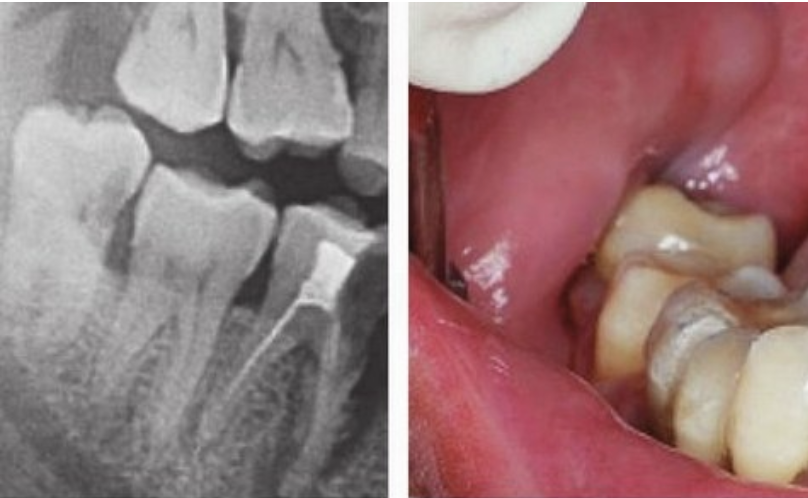

③拔除斜長、橫長或埋在骨頭里的下頜智齒,難度系數(shù):★★★★

其實,這些就是我們俗稱的阻生牙。

這一類智齒比較難拔,基本上都是微創(chuàng)手術(shù)了,但也需要切開牙齦操作,手術(shù)難度還是不低的。因此價格相比前兩種手術(shù)會高一些。

下頜智齒水平生長